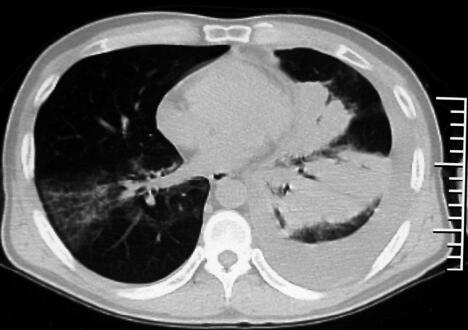

经莫西沙星治疗6天后患者仍有发热,体温稍降低,但仍可达38℃,双肺仍可闻及广泛湿啰音,双下肺可闻及散在干鸣音,气短较前加重。辅助检查回报:①血常规:白细胞计数10.5×109/L,中性粒细胞百分比85%,淋巴细胞百分比12%;②复查血清各种抗体(支原体、衣原体、军团菌)均为阴性,结核抗体阴性,PPD阴性;③痰细菌培养:未生长细菌;痰真菌培养阴性;④胸腔彩超:左侧胸腔积液;⑤胸水化验:胸腔积液常规:黄色微浊胸水,李凡他试验(+),细胞计数700×106/L;胸水生化:蛋白38.5g/L,ADA 78U/L;⑥胸部CT(治疗1周后):双肺仍可见斑片影,左肺实变影,左侧胸腔积液(图2)。

图2

患者拟诊为CAP,应用广谱抗生素莫西沙星,经过适当的抗感染治疗但病情无明显好转,此时应该考虑两个问题:①是否为特殊病原体感染?②是否是非感染性疾病?根据患者的临床特点及胸部CT表现,目前仍考虑为肺部感染性疾病,注意特殊病原体感染的可能性。患者结核抗体阴性,反复留痰查结核杆菌阴性,两次查肺炎支原体抗体、衣原体抗体、军团菌抗体阴性,以上非典型病原体感染的可能性不大,应注意其他病原感染可能,因此,重新深入询问病史特别是个人史并进行有针对性的检查非常重要。